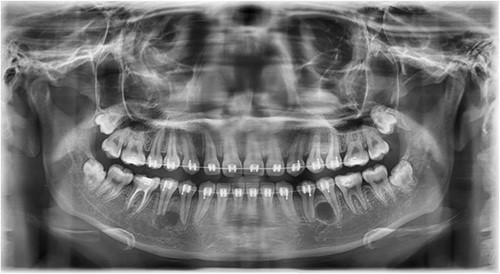

A Neumann full-thickness buccal flap was utilized to remove these during the course of orthodontic treatment. The shortcoming of the buccal surgical removal approach is that although it is better for visualization, it poses a high risk of trauma to the adjacent teeth or nerves [4, 5]. As the premolar was being removed on the right side, there was a fracture of the root apex (Fig. 2). On the left side, the premolar bud could be removed without any trauma to the adjacent tooth roots. After months of follow-up, there was normal bone formation, and no other symptoms were identified (Fig. 3).

Follow-up panoramic image 1-year after removal of the supernumerary premolars.